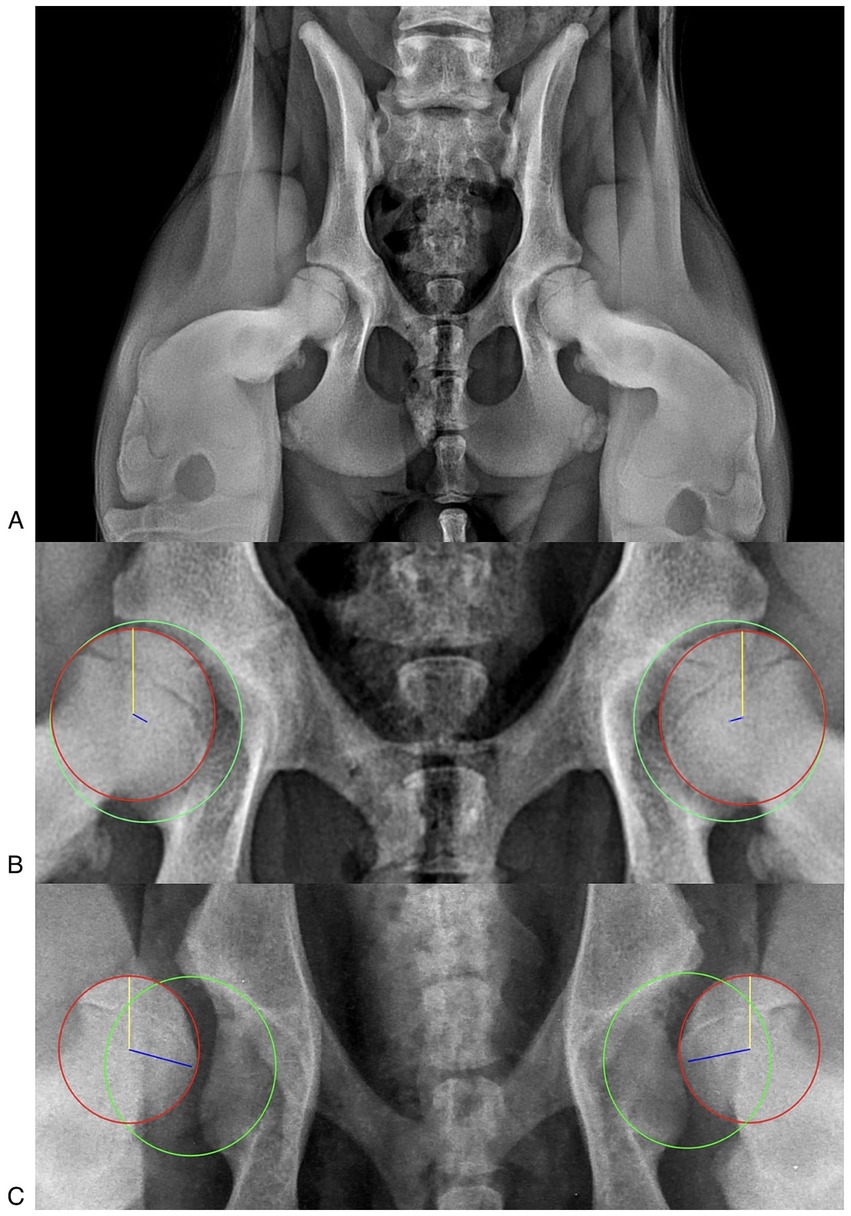

Introduction. The Vezzoni-Modified Badertscher Distension Device (VMBDD) technique is a radiographic method to assess hip joint laxity and is widely adopted in Europe. While the intra-observer and inter-observer variability of the Laxity Index (LI) measured on stress radiographs obtained with the VMBDD technique has been reported, it has never been evaluated in a large cohort of patients. The aim of our study is to assess the repeatability and reproducibility of the Laxity Index measured on stress radiographs obtained using the VMBDD technique in a large cohort of dogs. Methods. Stress-radiographs obtained with the VMBDD method of medium to large breed dogs, aged between 4.5 and 6 months, presented from 2021 to 2024 for screening of hip dysplasia were analyzed. The LI for each hip was blindly measured by three observers with different experience. Intra-and inter-observer significant variability was evaluated to assess repeatability and reproducibility of the LI, respectively. Statistical testing was performed and a p-value < 0.05 was considered significant. Inter-observer and intra-observer Intraclass Correlation Coefficients (ICCs) were evaluated. Results. One-hundred and ninety-five stress-radiographs (390 hip joints) were included. The inter-observer ICC showed moderate agreement (ICC = 0.55, 95% CI 0.50–0.59). EMMeans indicated that Observer 3 consistently provided higher LI values compared to Observers 1 and 2 across all time points (e.g., at T1: 0.484 vs 0.410 and 0.438, p-value < 0.001 for Observer 1 vs Observer 3). The repeatability within each observer were excellent for all three observers (Observer 1: ICC = 0.94, 95% CI 0.93–0.96; Observer 2: ICC = 0.99, 95% CI 0.99–0.99; Observer 3: ICC = 0.95, 95% CI 0.94–0.96). Conclusions. In-house evaluation of the LI on stress-radiographs obtained with the VMBDD technique was a high repeatable procedure, but it was a moderate reproducible measurement due to systematic upward bias by observer with less experience. Nevertheless, the mean differences could be negligible in a clinical setting due to the low impact on the definitive diagnosis.